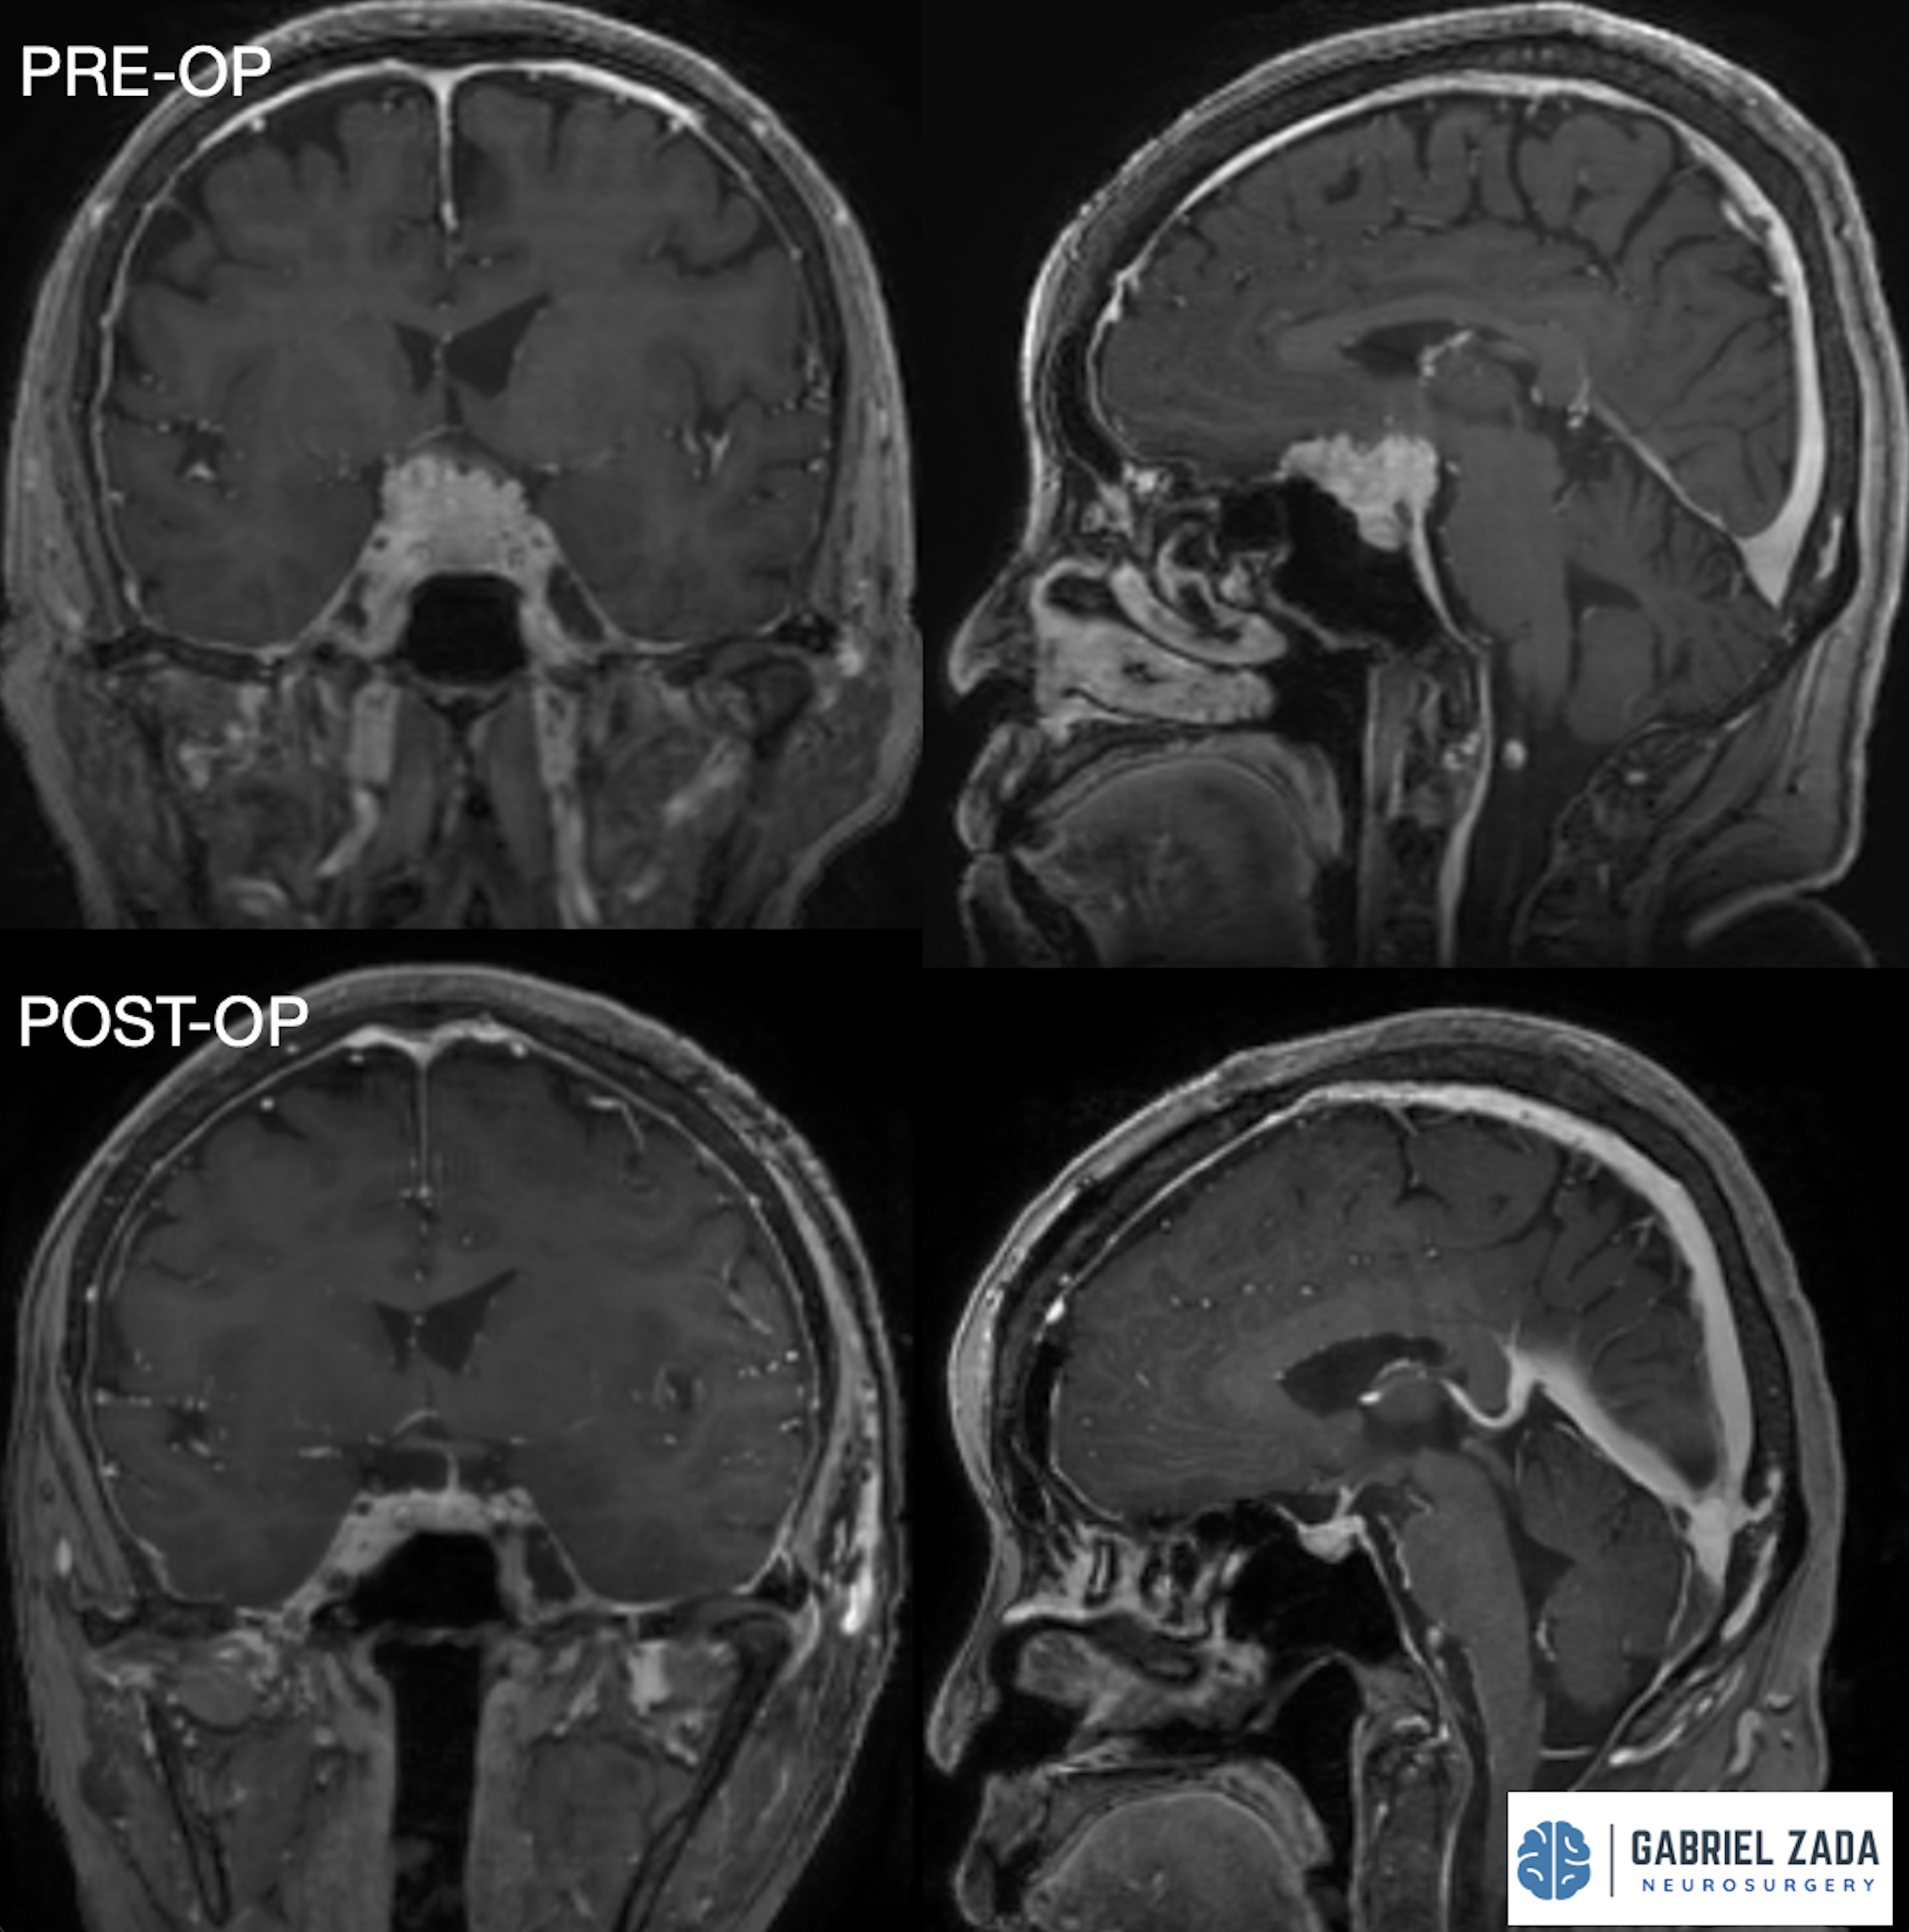

Explore this comprehensive gallery featuring pre‑ and post‑operative imaging of patients with skull‑base tumors treated by Gabriel Zada, MD, MS, FAANS, FACS. These cases highlight Dr. Zada’s expertise in advanced neurosurgical techniques and outcomes.

*Representative cases shown for educational purposes. All images de-identified. Individual results vary.